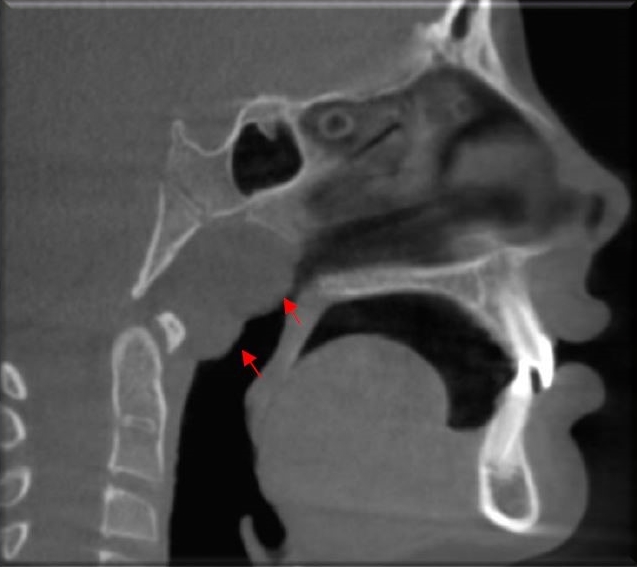

161 - Grados de hipertrofia adenoidea evaluadas por tomografía computarizada de haz cónico - IDM